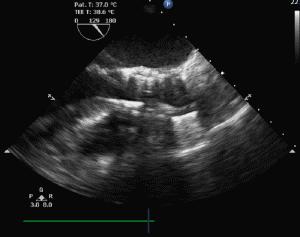

患者女,85岁,术中经食道超声评估,为三叶瓣,重度钙化,瓣环径20mm,左室流出道19mm,法式窦29mm,STJ21.5mm较小,双冠高度可。